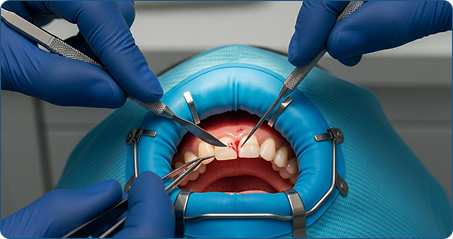

La chirurgia orale è un termine generico che comprende tutte le procedure chirurgiche relative alla bocca, ai denti, alle gengive e alle ossa mascellari. Le principali aree di intervento includono:

La chirurgia orale richiede una conoscenza approfondita dell'anatomia e delle patologie della cavità orale, nonché competenze avanzate in anestesia e gestione post-operatoria.

Gli interventi vengono eseguiti da odontoiatri o chirurghi maxillo-facciali a seconda del caso, in stretta collaborazione con altre figure professionali (ortodontisti e protesisti) per garantire il miglior risultato funzionale ed estetico.